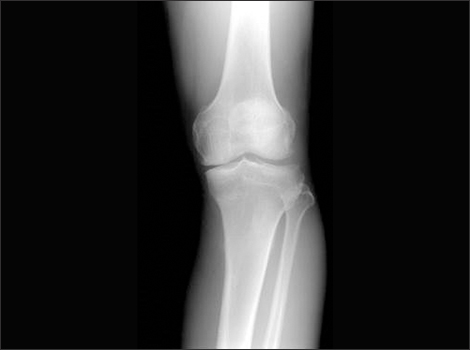

무릎의 연골도 대부분 관절과 동일하게 뼈를 매끄럽고 마찰이 덜가게 생성해 주는 미끄러운 연골 층으로 둘러 축적되어 있어요. 뿐 아니라, 무릎 중앙에는 부가적인 충격 흡수를 전달하는 반월상 연골이라고 하는 두 개의 고무질 반원형 연골 조각이 있어요.

뼈랑 뼈 사이에는 연골이 있어요. 연골이 망가진다는 소리는 뼈랑 뼈가 바로 닫게 된다는 소리 이라고 합니다. 그러면 통증이 발생하게 되죠. 무릎을 움직일 때 마다 통증이 생기고 불편해져요. 무릎 운동이 뻐근해지고 힘들어져요.

환자의 나이가 젋고 망가진 연골의 크기가 작은 경우 2cm 이하일때 시행하는 방법으로 관절내시경을 통하여 닳아 없어진 연골부위에 작은 구멍을 3~4mm 간격으로 생성시켜서 구멍이 회복되는 과정에서 연골이 재생되는 과정을 유도하는 원리이라고 합니다.